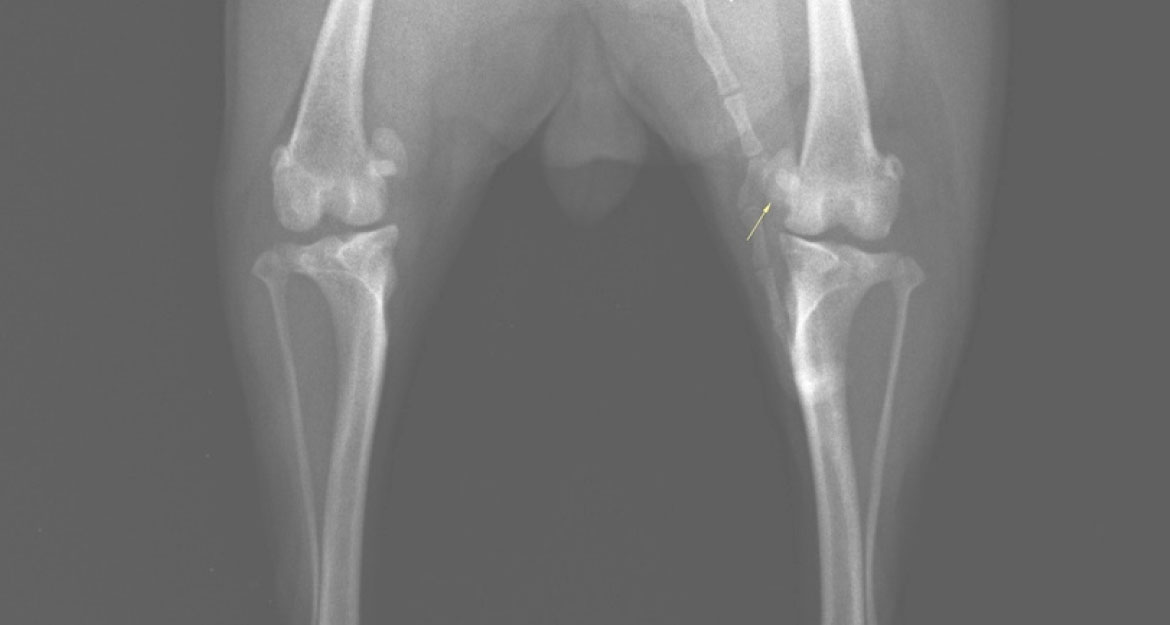

内方脱臼(右後肢)

-

Before

膝蓋骨が内側(内方)に変位しています -

After

膝蓋骨が正常な位置(正中)に整復されています